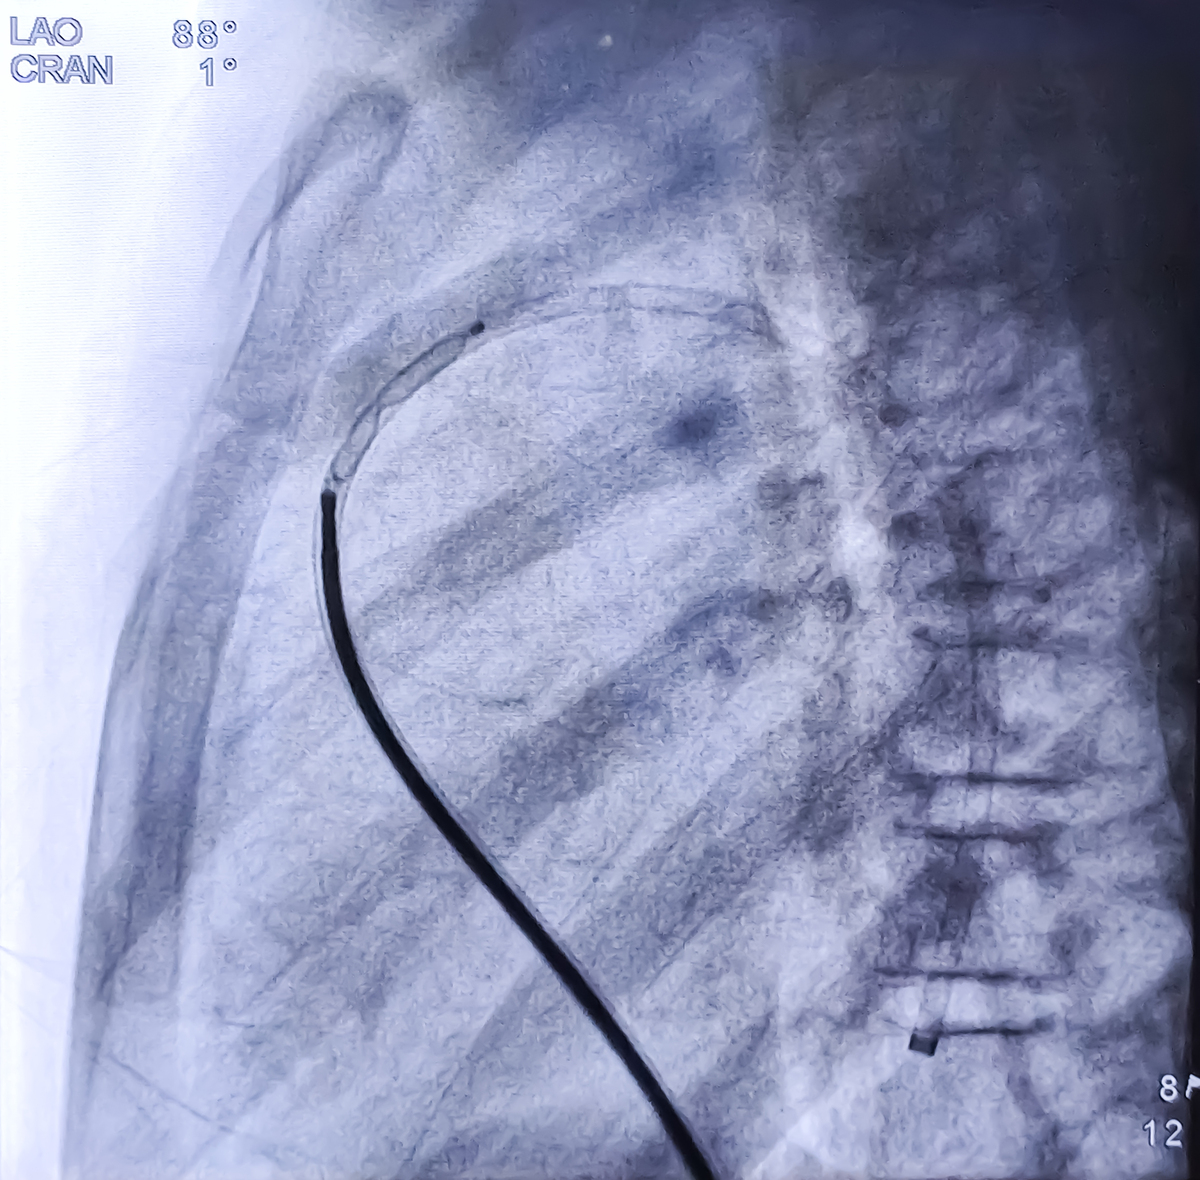

Translation: Digital Subtraction Angiography (DSA) is the gold standard for diagnosing carotid artery disease. However, as an invasive examination, DSA involves radiation and is relatively expensive. Moreover, it cannot display neovascularization within plaques and small ulcers.